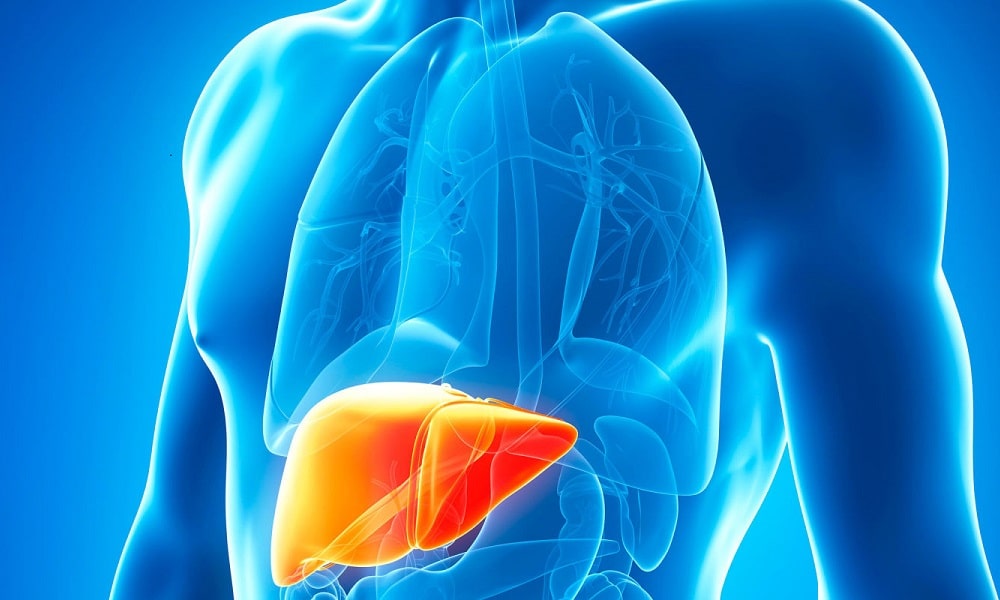

Изображения заболеваний печени: признаки и симптомы